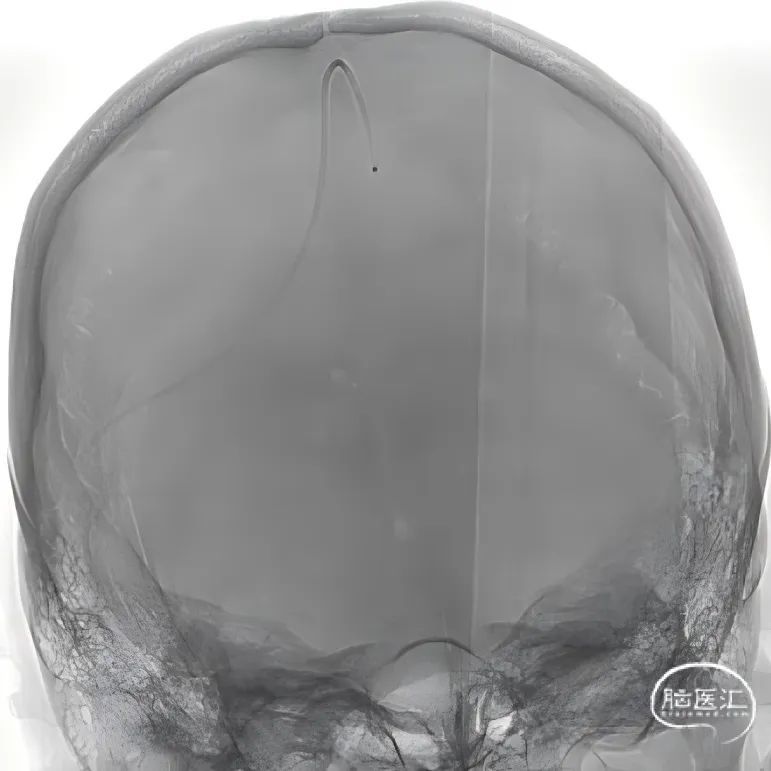

术前CT:左侧颞叶低密度病变考虑梗死灶,后续梗死灶不断增大合并出血。

术前CTV:左侧颈内静脉、乙状窦、横窦闭塞,血栓形成。

术前复查头部CT。

股动脉穿刺置5F鞘做静脉窦造影,股静脉穿刺置8F鞘进行治疗。260cm泥鳅导丝,将132cm 0.068" React™导管送至上矢状窦前部,尽量推高长鞘,增加支撑力。

经中间管手推造影,确认血栓位置。